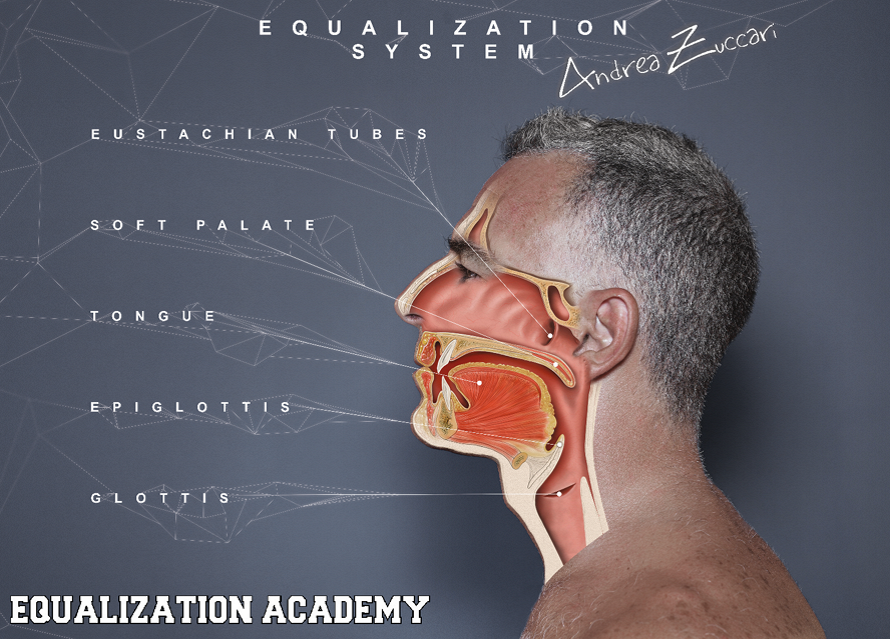

Zunächst ein bisschen Anatomie:

1. Am Druckausgleich beteiligte Organe bzw. Körperstrukturen

Am Druckausgleich beteiligte Organe:

- Glottis (Stimmritze, engl. glottis)

Die Stimmritze stellt den Hohlraum zwischen den am Stellknorpel befestigten Stimmbändern dar und ist mit der Lunge und der Mundhöhle verbunden.

- Zunge (engl. tongue)

Die Zunge spielt eine wichtige Rolle beim Druckausgleich, denn sie kann die Mundhöhle an verschiedenen Positionen in einen vorderen und hinteren Bereich unterteilen. Dies wird später bei den „Stimmübungen“ klarer.

- Weicher Gaumen (Palatum molle, engl. soft palate)

Der weiche Gaumen ist Teil des Mundhöhlendaches und die Fortsetzung des harten Gaumens. Er besteht aus der Uvula (dem sogenannten Zäpfchen) und dem Gaumensegel (Velum palatini). Um das Gaumensegel liegen drei kleine Muskeln. Zwei davon, nämlich der Muskulus tensor veli palatini und der Muskulus levator veli palatini, werden später nochmals gesondert erwähnt – also merken! Der gesamte weiche Gaumen spielt eine maßgebliche Rolle beim Druckausgleich, da er die Mundhöhle mit der Nasenhöhle verbindet.

- Eustach’sche Röhre (Tuba auditiva, engl. Eustachian tube)

Die Tube ist eine 30 – 35 mm lange, mit Flimmerepithel ausgekleidete, Röhre, die das Mittelohr und den Nasenrachenraum verbindet. Ohne eine ausreichende Belüftungsfunktion ist der Druckausgleich unmöglich, da dies der einzige Zugang zum Mittelohr ist. Im Normalzustand ist die Tube geschlossen, öffnet sich jedoch beim Schlucken, Gähnen oder bestimmten Lauten und natürlich beim Druckausgleich.

- Epiglottis (Kehldeckel, engl. epiglottis)

Der Kehldeckel ist eine mit Schleimhaut überzogene Knorpelplatte und verschließt beim Schlucken den Weg zur Lunge. Passiert dies nicht oder unvollständig, verschlucken wir uns und bekommen etwas „in den falschen Hals“. Die Epiglottis ist beim Druckausgleich nur beteiligt, wenn dieser durch Schlucken bewerkstelligt wird.